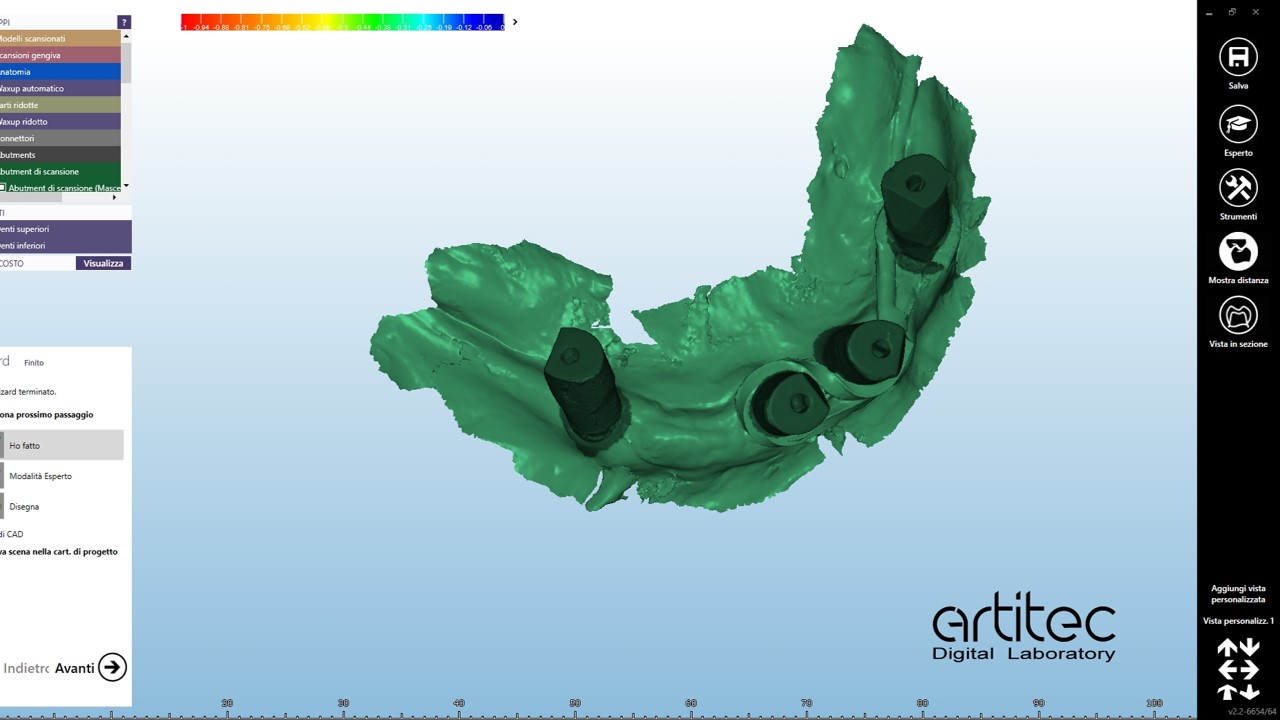

foto 09 scan body superiore

foto 10 scan body superiore allineati- best fit

foto 11 scan body inferiore

foto 12 scan body inferiore allineati

La fase protesica inizia con la ribasatura delle protesi provvisorie per rilevare la corretta anatomia della cresta. Quindi si procede a scansionare con scansione intraorale le impronte ottenute fuori dal cavo orale, poi le protesi provvisorie ribasate ricollocate nel cavo orale e la loro occlusione. Infine, si scansionano le creste edentule dopo aver posizionato gli scan body per tecnica digitale per rilevare la posizione degli impianti. Per la pianificazione sono scattate delle fotografie intraorali ed extraorali per la definizione dei limiti perimetrali del volto al fine di poter eseguire la programmazione del caso tramite il software di previsualizzazione. Le scansioni così ottenute sono poi inviate al laboratorio per la realizzazione di un prototipo delle protesi in prova.